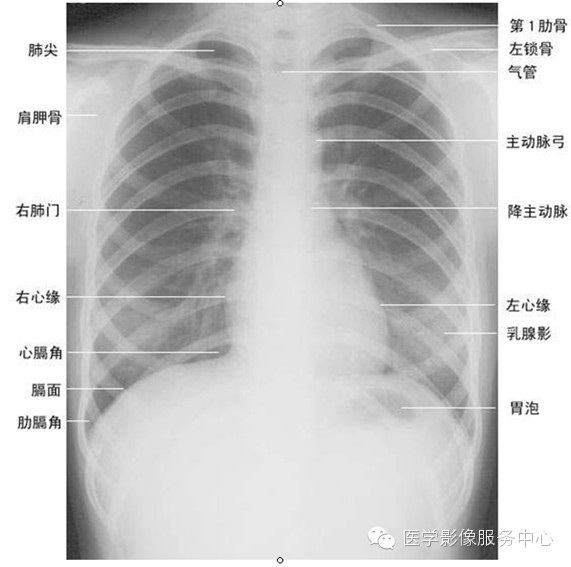

很多初学者(包括部分高年资医生)观察胸片时有漏诊,主要原因是对胸片观察死角不太注意。根据偶的经验,正位胸片有10大观察死角:

影像观片原则:总体印象、分部观察、注意死角、左右对比、前后对照。